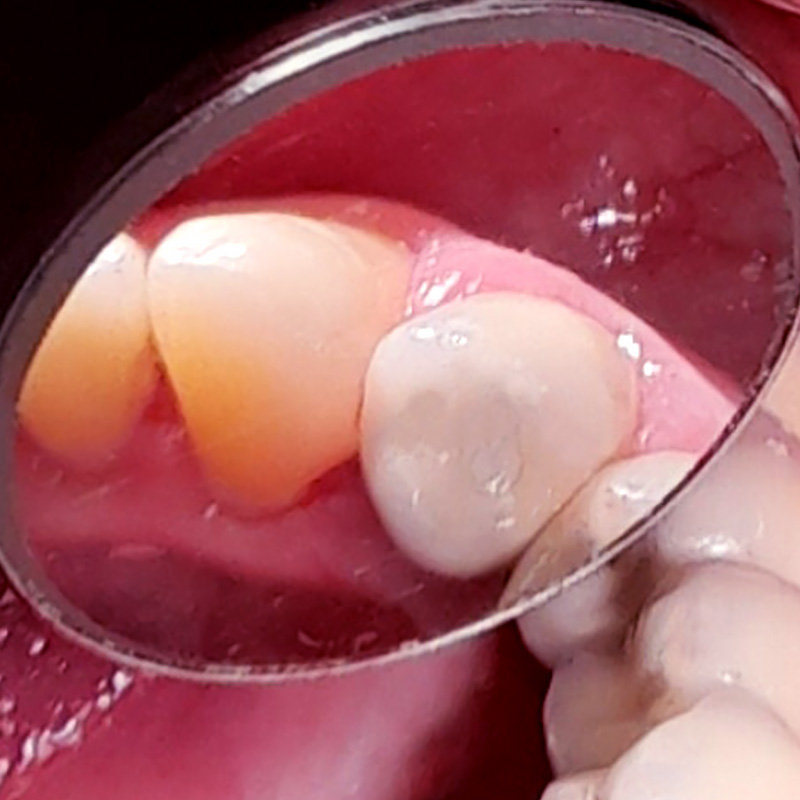

В нашу клинику обратился пациент с жалобами на дискомфорт при приёме холодных продуктов питания в области верхнего переднего зуба слева. При осмотре обнаружена кариозная полость без нарушения режущего края. После обработки полости под контролем кариес-маркера, был выявлен глубокий кариес, сообщающийся с пульпарной камерой, рог пульпы кровоточил.

В ходе лечения были проведены следующие работы:

- эндодонтическое лечение с использованием системы коффердам

- поставлена высокоэстетичная пломба Vitremer A3

- микроконтурирование и макроконтурирование пломбы